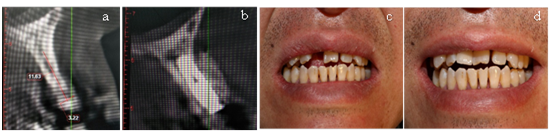

A 48-year-old male patient settled in the plateau area, with a chief complaint of implant denture restoration. The maxillary right lateral incisor of the patient was removed due to periodontitis. (Health status: smoking for 21 years, fasting blood glucose: 7.2mmol/L). Surgical approach: we made a midline incision on the edentulous alveolar crest, adding a vertical loose incision. Moreover, the full thick mucoperiosteum flap was developed. We placed an Osstem implant (3.3*10mm) after flap opened. The buccal bone defect was surgically treated by placing bone scraps and bone substitutes (Bio-Oss®) and covered with a resorbable collagen membrane (Bio-Gide®). Double-layer membrane technique was used to ensure longer barrier function (Bosshard and Schenk, 2010). CBCT showed preoperative and postoperative results (Figure 1a) (Figure 1b). Clinical photographs of preoperative and of 6 months after the operation (Figure 1c) (Figure 1d).

Figure 1 (a) CBCT of preoperation. (b) CBCT of postoperation. (c) Clinical photograph of preoperation. (d) Clinical photograph of 6 months after the operation.